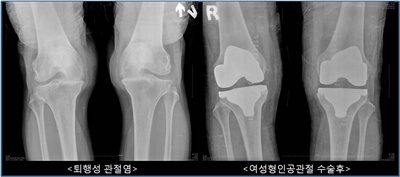

과거에는 남녀 성별을 고려하지 않고 남성의 무릎에 맞춰 제작된 인공관절로 수술이 이루어져왔다. 따라서 여성 환자들의 경우에는 본인의 무릎보다 큰 인공관절로 수술 받을 경우, 무릎 앞부분에 불필요한 마찰이 생겨 통증을 느끼는 경우가 많았고, 움직일 때도 마치 내 무릎이 아닌 것 같은 이물감이 생겼다. 이러한 여성 환자의 불편함을 해소하기 위해 개발된 것이 ‘여성형 인공관절’인데, 여성의 무릎 모양 및 크기와 흡사하게 설계되었기 때문에 무릎의 움직임이 훨씬 자연스러워졌고 무릎 앞쪽의 통증도 많이 줄어들어 환자들의 만족도가 높아졌다.